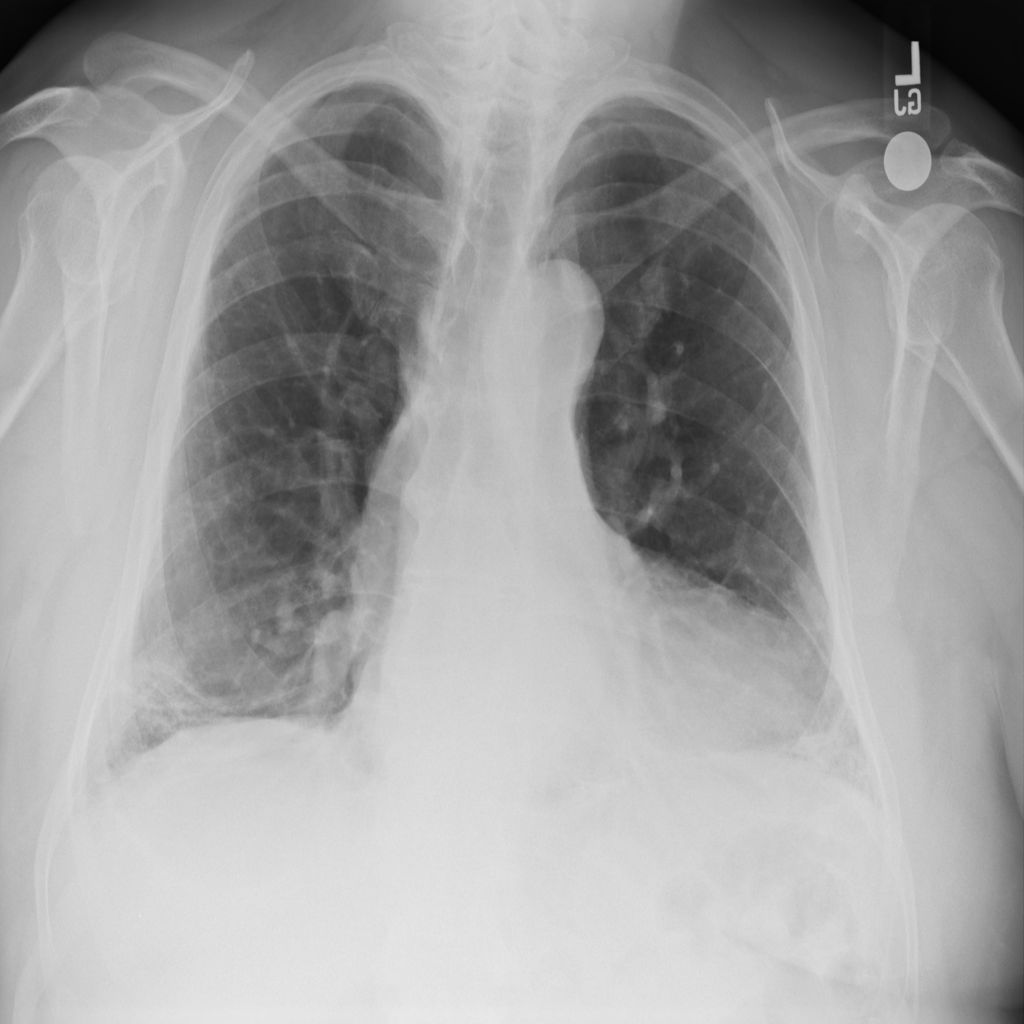

PAT-E960 · IMG-002Fibrosis

PAT-E960 · IMG-002

PA